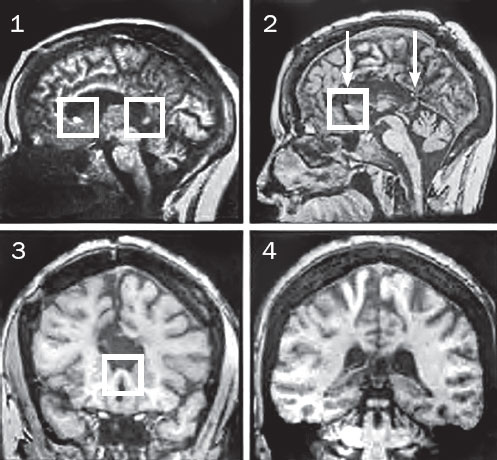

Илл. 8. МРТ-снимки мозга пациентки В. П. 1984 и 2000 года. Белыми квадратами выделены области интенсивного сигнала, которые наблюдались на обоих концах мозолистого тела в 1984 году (слайд 1) и на ростральном конце в 2000 году (слайд 2). Стрелки на слайде 2 указывают локализацию фронтальных срезов, показанных на слайдах 3 и 4. На слайде 3 показан срез через область интенсивного сигнала, обнаруженную в передней части мозолистого тела, где отчетливо видны сохранившиеся волокна. На слайде 4 показан срез через ту область задней части мозолистого тела, где в 1984 году мы наблюдали интенсивный сигнал. Здесь волокна явно рассечены.